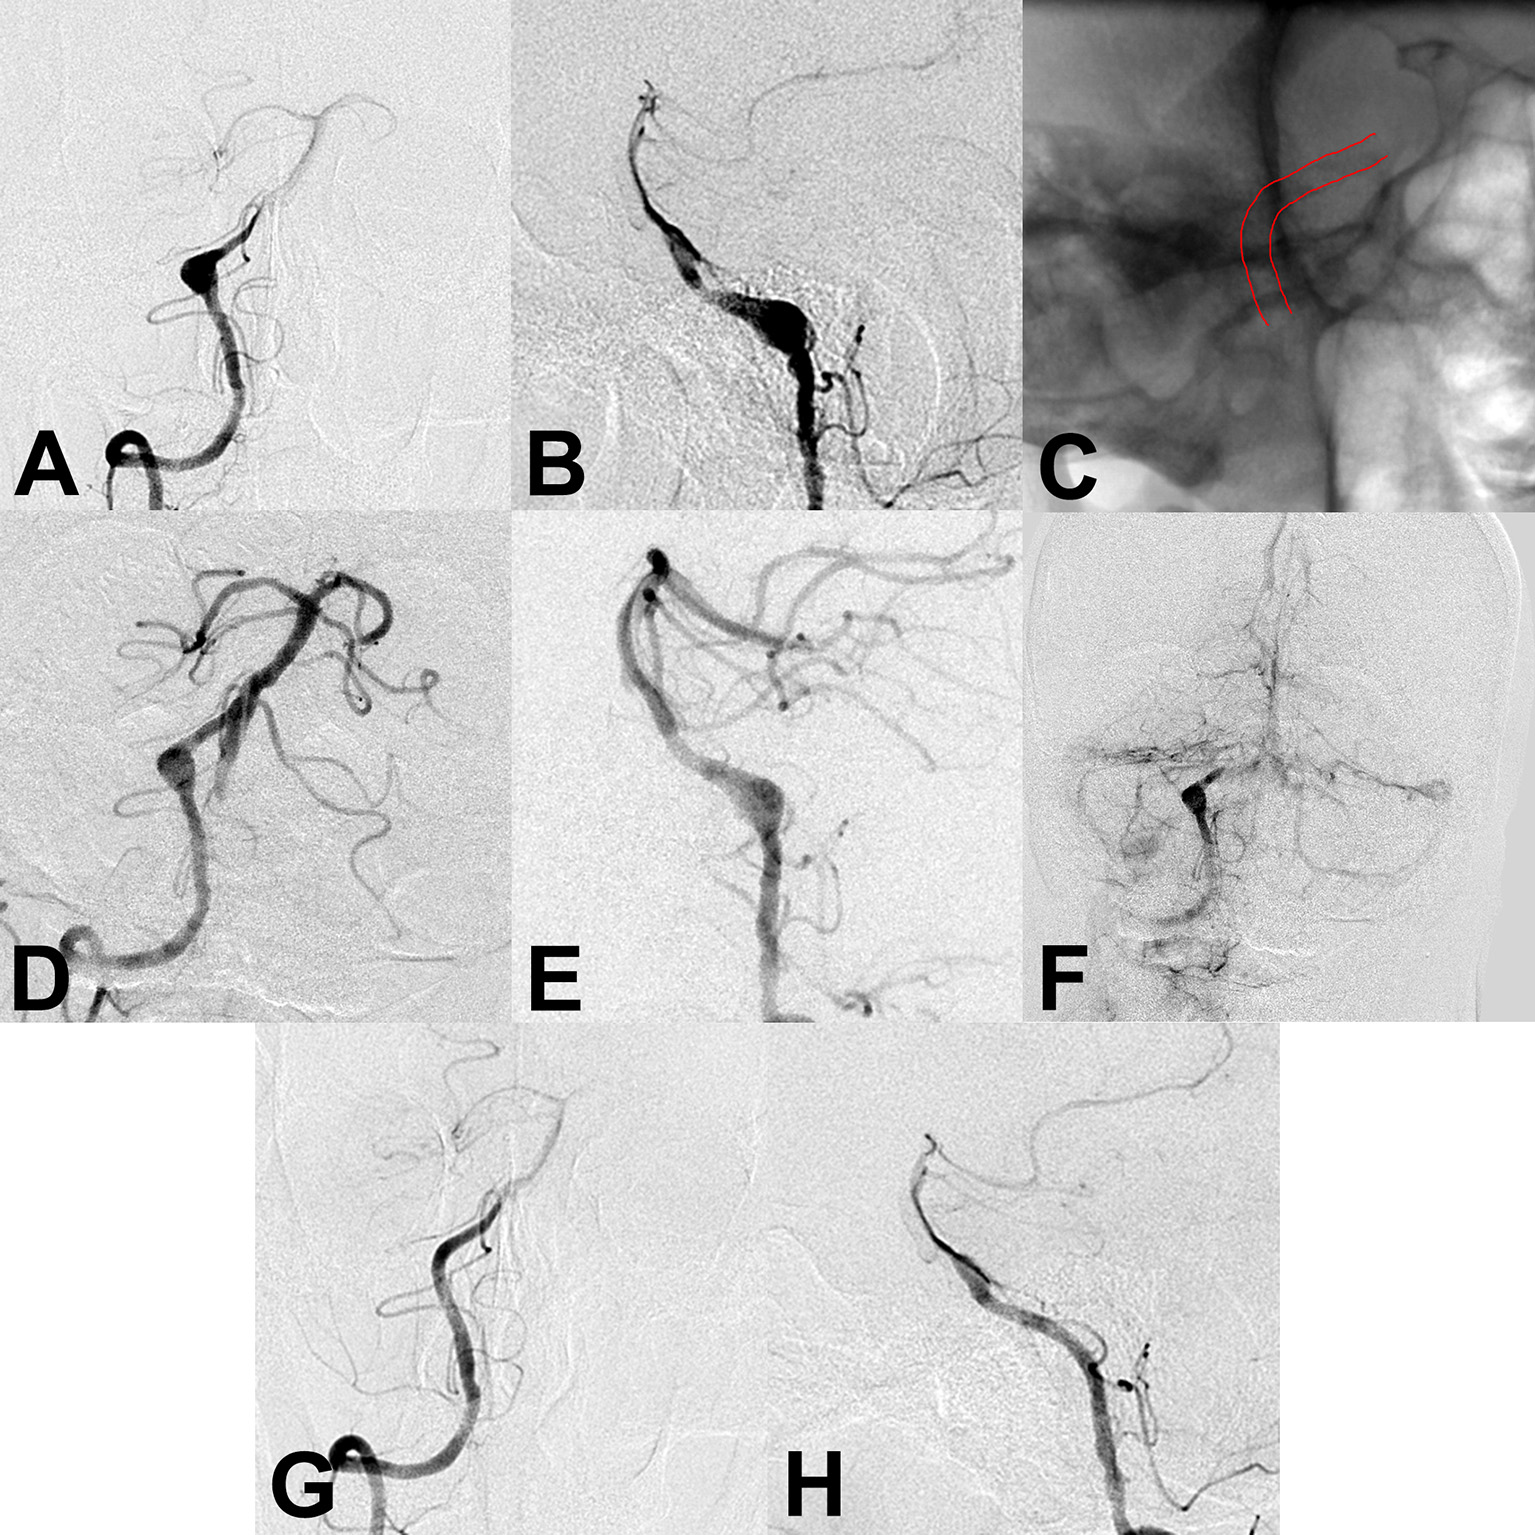

Figure 2

(A,B) Preoperative angiography showed an unruptured vertebral artery fusiform aneurysm. (C) Intraoperative angiography showed successful deployment of a flow diverter stent (lines). (D–F) Angiography immediately after the procedure showed a residual aneurysm with significant stasis. (G,H) Follow-up angiography 6 months after the procedure showed complete aneurysm obliteration.